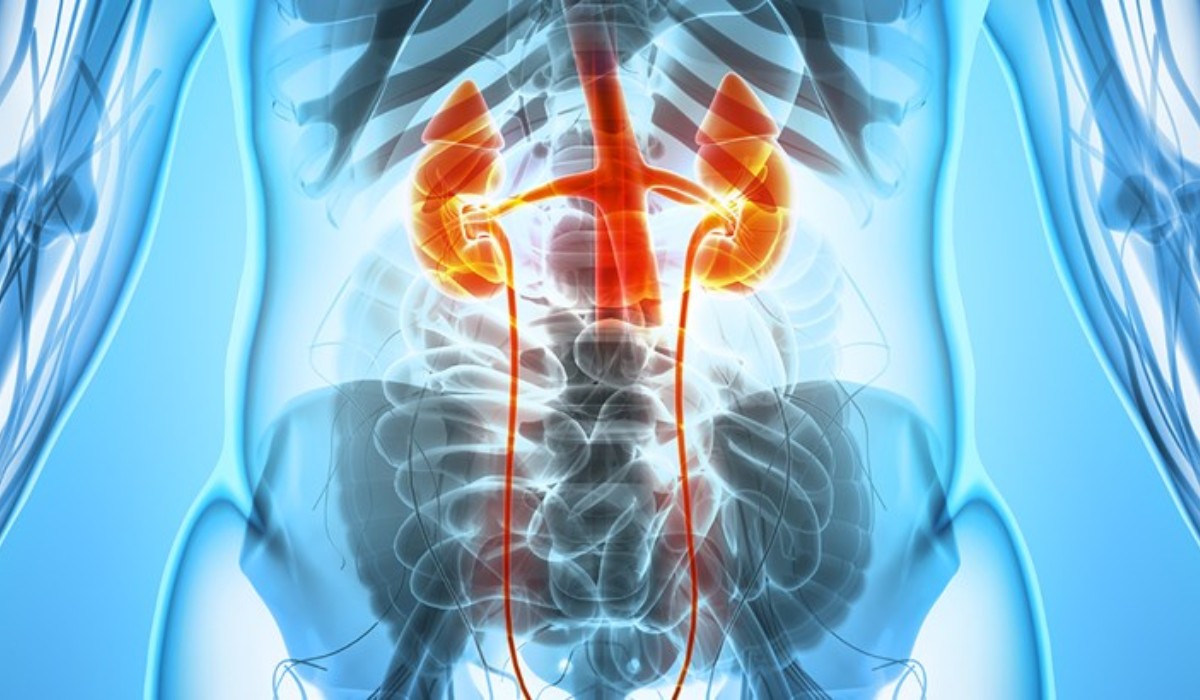

"I had an excellent experience at the urology clinic. The staff was very friendly and professional, and the doctor was knowledgeable and thorough in their examination. I received the care and attention I needed to address my urological concerns, and I highly recommend this clinic to anyone seeking quality